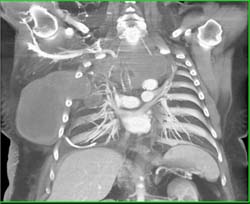

Pretty Bypass Graft and Incredible Pulmonary Arteriovenous Malformation (AVM)